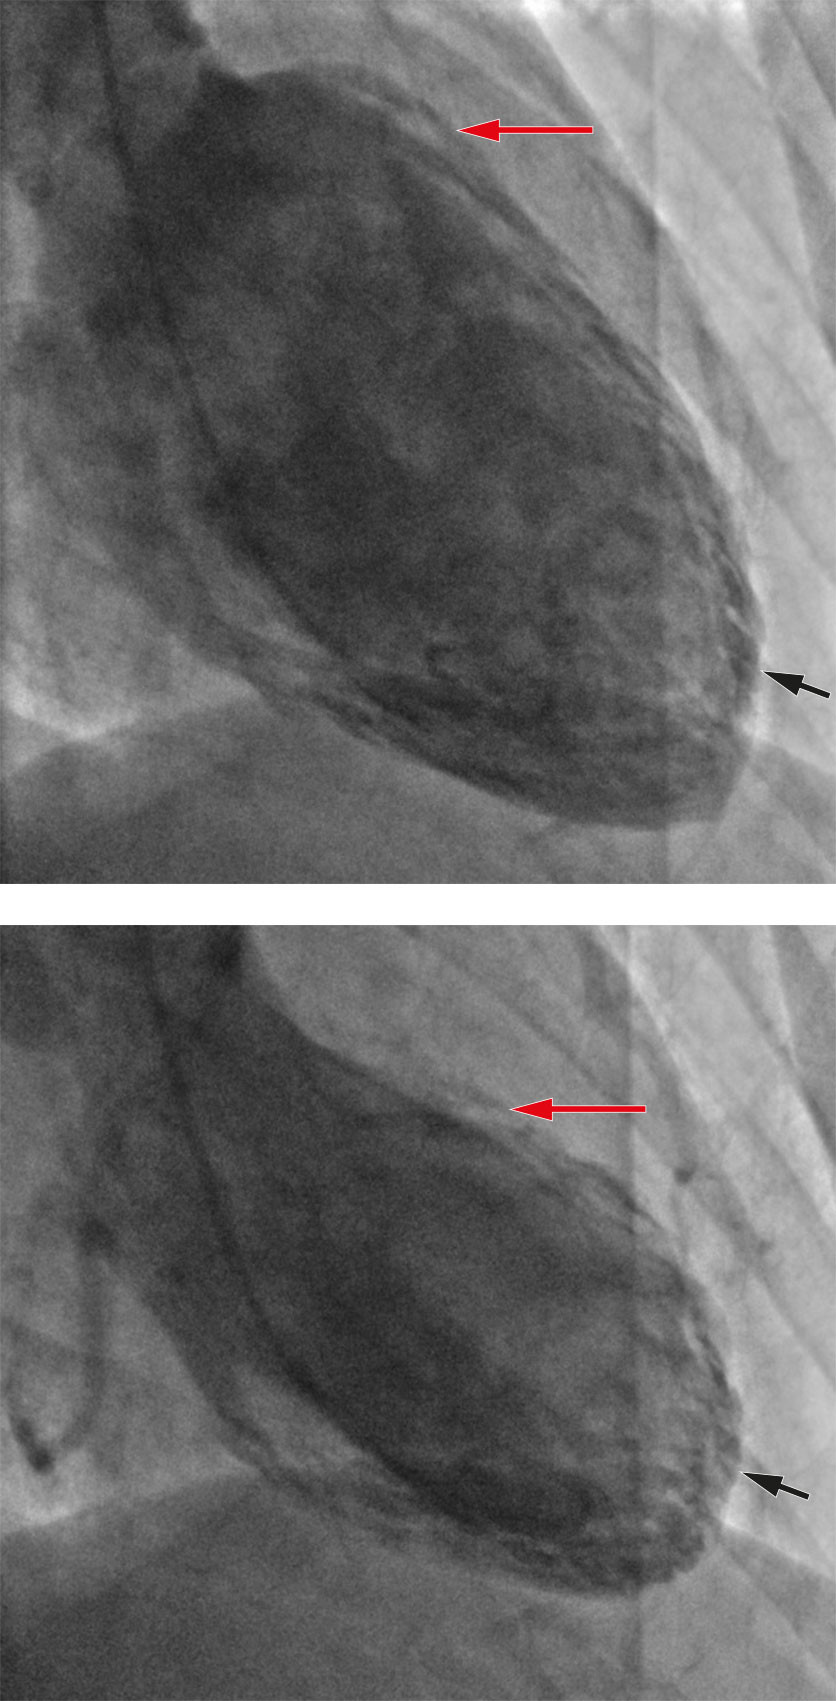

Koronarangiografi viste normale koronararterier, og ventrikulografi viste hypokinesi apikalt og hyperkontraktilitet basalt, typisk for takotsubosyndrom (Figur 2). Samme kveld ble det startet opp behandling med 1,25 mg ramipril.